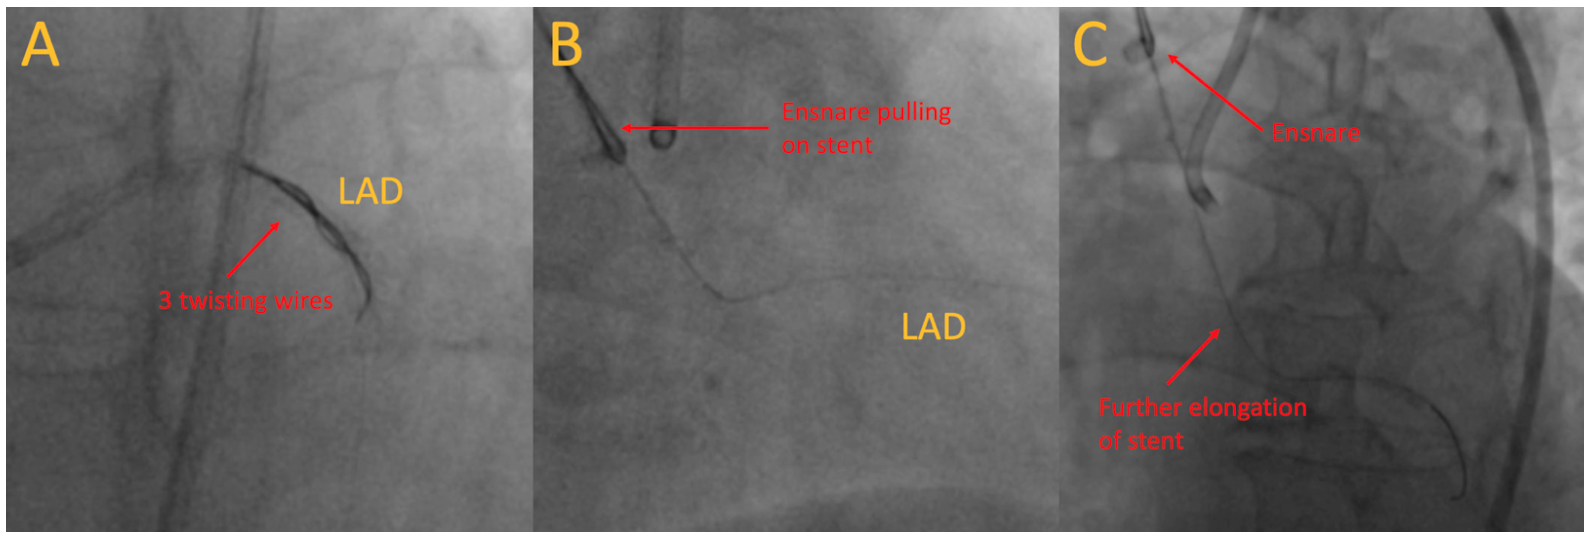

Subsequently, an EN Snare endovascular snare system (Merit Medical) was sent along the original true-lumen guidewire to pull the stents out. Initially, the protruding stent, along with the remaining stents inside the coronary artery, were moving out (Figure 2B; Video 2). However, with further pulling, the middle part of the stent weakened and further elongated to the verge of breaking (Figure 2C). With further pulling, the stent would break, risking both stent embolization and long stent protrusion inside the aorta.